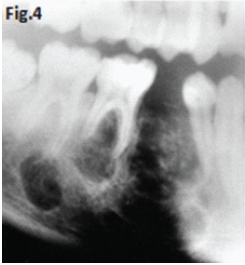

Fig 1 & 2: the large lesion of left mandible shows a honeycomb-like distribution of calcifications. The borders are corticated. The tumour has displaced the mandibular molar tooth. A histological diagnosis of calcifying epithelial odontogenic tumour (Pindborg Tumour) was made. Fig.3 shows a Pindborg tumour distal to left second premolar associated with displacement of the first molar tooth. Fig.4 shows a similar tumour with mixed lucency-opacity between right premolar and molar teeth. Figs 5 & 6 show coronal and axial CT views of a large Pindborg tumour affecting the right maxilla. Note the marked expansion and cortical destruction. Calcifying epithelial odontogenic tumour is a rare benign neoplasm, accounting for less than 1% of all odontogenic tumours. The average age at diagnosis is 40 years; however, the tumour can occur at any age. It occurs equally in males and females. Approximately two thirds of cases are reported to occur in the mandible. Most cases occur in the premolar-molar area and are commonly associated with an unerupted tooth. The tumour is a painless, slowly enlarging mass. Histologically the tumour has a very characteristic appearance. Sheets of polyhedral cells with well-defined eosinophilic cytoplasm and hyperchromatic nuclei are featured. Amyloid and ringlike calcification may also be present. The tumour may be irregular or, in some cases, the cystic lesions may be well defined and corticated, whereas others appear ill defined. Small unilocular lesions may have a completely radiolucent centre (Fig.3). Others may have variable amounts of small flecks of calcifications scattered throughout. Larger lesions have a multilocular or honeycomb appearance. The tumour can displace and often prevent the eruption of teeth. Radiologically the tumour may be very similar to the calcifying odontogenic cyst, adenomatoid odontogenic tumour and ameloblastic fibro-odontoma.